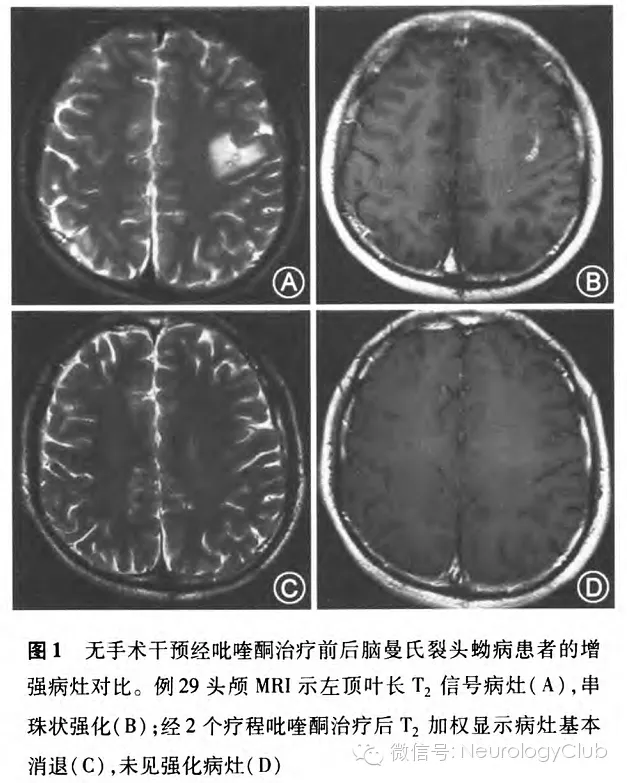

共有24例患者在不同阶段进行了CT扫描。CT扫描显示低密度肿块状病变,13例患者出现同侧脑室扩张,6例显示同侧脑室受压,18例CT扫描显示分散在病变区的细小针尖样、点状钙化影的存在(图2A)。

所有患者均接受至少2次MRI扫描(在诊断时和治疗后)。42例患者中单侧强化孤立病灶者41例,占97.6%(41/42),双侧强化病灶者l例,占2.4%(1/42)。幕上病灶40例,占95.2%(40/42),幕下病灶2例,占4.8%(2/42)。病灶主要以额顶叶为主,占69.0%(29/42)。头颅MRI病灶表现为T1加权像低信号(图2B),T2加权像高信号,部分患者可见点状的混杂信号(图2C)。增强MRI显示38例患者病灶呈聚集的多发小环状强化,典型者表现为绳结状(图2D);14例患者病灶呈隧道样强化,特别在矢状位和冠状位明显(图2E),隧道一般长l-5cm,宽0.3-1.2cm,T1加权像为低信号、稍高信号或等信号,T2加权像为高信号。此外,随访MRI发现13例患者存在新旧病灶迁移(图2F),从额顶到顶枕5例;从额顶到颞叶3例;从顶叶到小脑半球2例;从左额叶到右额叶再到枕叶l例;从脑干到丘脑到顶叶1例;从基底节到额顶到胼胝体1例。